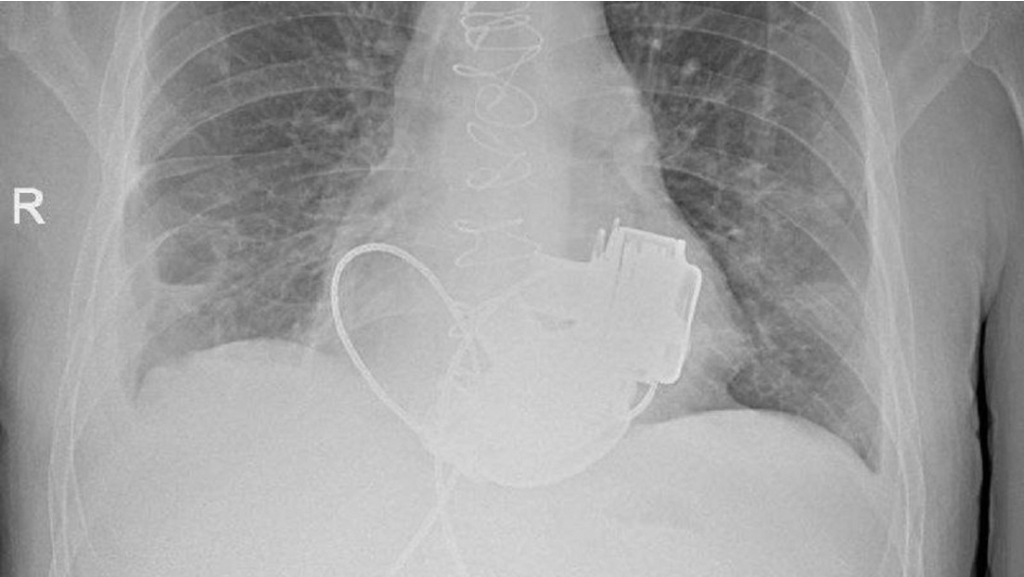

Diversas complicaciones graves impidieron un trasplante de corazón inmediato, lo que llevó al equipo médico del hospital a optar por una solución excepcional: implantar dos dispositivos de asistencia ventricular. La colocación de los aparatos, que reemplazan la función de los ventrículos dañados del corazón para bombear sangre al cuerpo, fue realizada en noviembre del año pasado.

Gennady Khubulava, cirujano cardiovascular jefe del Comité de Salud de San Petersburgo, detalló que la cirugía duró unas cuatro horas y el principal desafío fue lograr la sincronización de ambos ventrículos artificiales. Asimismo, afirmó que el éxito del procedimiento es una evidencia del alto nivel de desarrollo de la cirugía cardíaca en la ciudad.